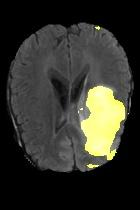

Current unsupervised anomaly localization approaches rely on generative models to learn the distribution of normal images, which is later used to identify potential anomalous regions derived from errors on the reconstructed images. However, a main limitation of nearly all prior literature is the need of employing anomalous images to set a class-specific threshold to locate the anomalies. This limits their usability in realistic scenarios, where only normal data is typically accessible. Despite this major drawback, only a handful of works have addressed this limitation, by integrating supervision on attention maps during training. In this work, we propose a novel formulation that does not require accessing images with abnormalities to define the threshold. Furthermore, and in contrast to very recent work, the proposed constraint is formulated in a more principled manner, leveraging well-known knowledge in constrained optimization. In particular, the equality constraint on the attention maps in prior work is replaced by an inequality constraint, which allows more flexibility. In addition, to address the limitations of penalty-based functions we employ an extension of the popular log-barrier methods to handle the constraint. Comprehensive experiments on the popular BRATS'19 dataset demonstrate that the proposed approach substantially outperforms relevant literature, establishing new state-of-the-art results for unsupervised lesion segmentation.

翻译:目前未受监督的异常本地化方法依靠基因模型来了解正常图像的分布,这些模型后来被用于确定从重建图像错误中得出的潜在异常区域。然而,几乎所有先前文献的主要局限性是,需要使用异常图像来设定一个特定等级的阈值以定位异常。这限制了其在现实情景中的可用性,在现实情景中,只有通常能获取正常数据。尽管存在这一重大缺陷,但只有少数作品通过在培训中整合对关注地图的监督,解决了这一局限性。在这项工作中,我们提议了一种新颖的提法,不要求使用异常图像来界定阈值。此外,与最近的工作相反,拟议的限制是以更加有原则的方式拟订的,在限制优化时利用众所周知的知识。特别是,先前工作中对关注地图的平等性制约被一种不平等性制约所取代,这允许更大的灵活性。此外,为了解决基于惩罚的功能的局限性,我们采用了流行的日志障碍方法来应对这一制约。我们建议对流行的BRATS'19数据设置进行综合实验,这与最近的工作不同,因此,拟议的限制是以更加有原则的方式提出了限制,即拟议的方法大大地超越了相关的分段结果。